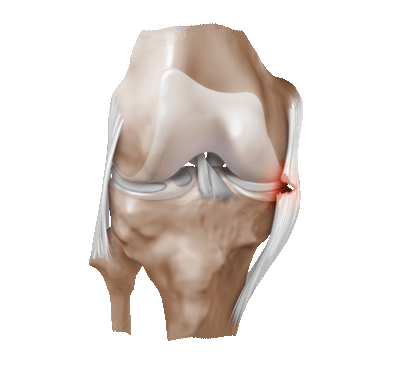

• Патологическая синовиальная складка (рис. 1)

• Медиопателлярная складка чаще всего становится патологической в результате локальной травмы внутреннего мыщелка бедра или надколеннико-бедренного сустава, когда эта складка становится механическим препятствием для нормальных движений в суставе, источником болевых ощущений и причиной износа прилежащих участков суставного хряща